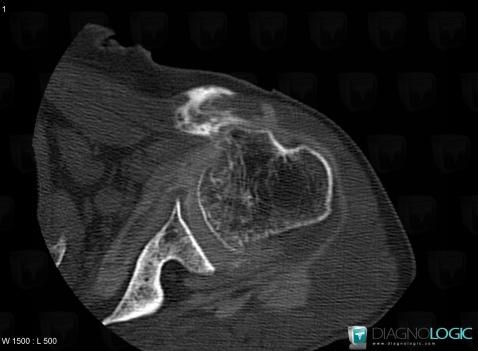

The images below illustrate this case for diagnoses Dislocation of the biceps brachii tendon, for the modalities (CT)

Dislocation-the biceps brachii tendon, Long head-biceps tendon, CT

Here is the specific information in the key image above:

- Diagnosis Dislocation of the biceps brachii tendon, Location(s) Long head of biceps tendon, with gamuts